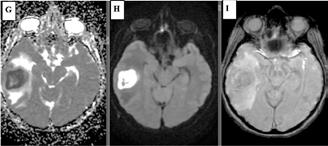

• Studiul opacifierii ramurilor corticale ale arterelor cerebrale medii (M4) drepte și stângi și a venelor cerebrale interne drepte și stângi (Fig.1).

Fig.1 ACTMS cranio-cerebrală, recon MIP în plan axial (a,b) și sagital (c): aspect normal; (a) opacifierea arterelor temporale dreaptă și stângă (săgeţi); (b) opaciferea ramurilor corticale ale arterelor cerebrale medii (M4)-săgeţi albe; opaciferea venelor cerebrale interne dreaptă și stângă (săgeţi negre-b și c).

În cazul opacifierii unilaterale a uneia dintre cele două artere cerebrale medii, diagnosticul de MC poate fi afirmată dacă este absentă opacifierea venelor cerebrale interne (Fig,2).